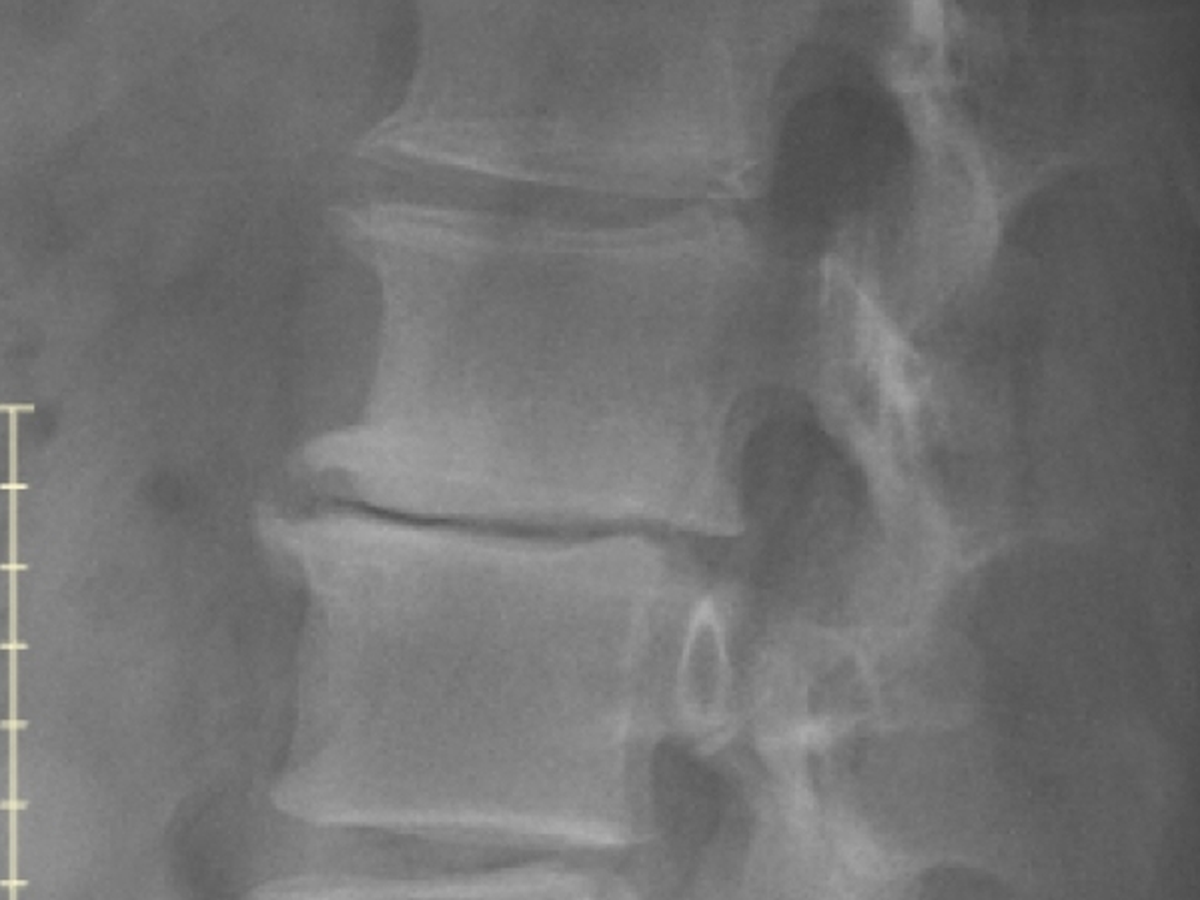

So, I was trying not to use this so much anymore. But, things have taken a turn for the worse. My surgeon had x-rays done on my lower back and they showed that two discs are almost completely gone and three others are close. So, I won't be cleared for work for the foreseeable future. I've only posted this from the beginning out of desperation and have only become more desperate. If you are able to help my appreciation would know no bounds.